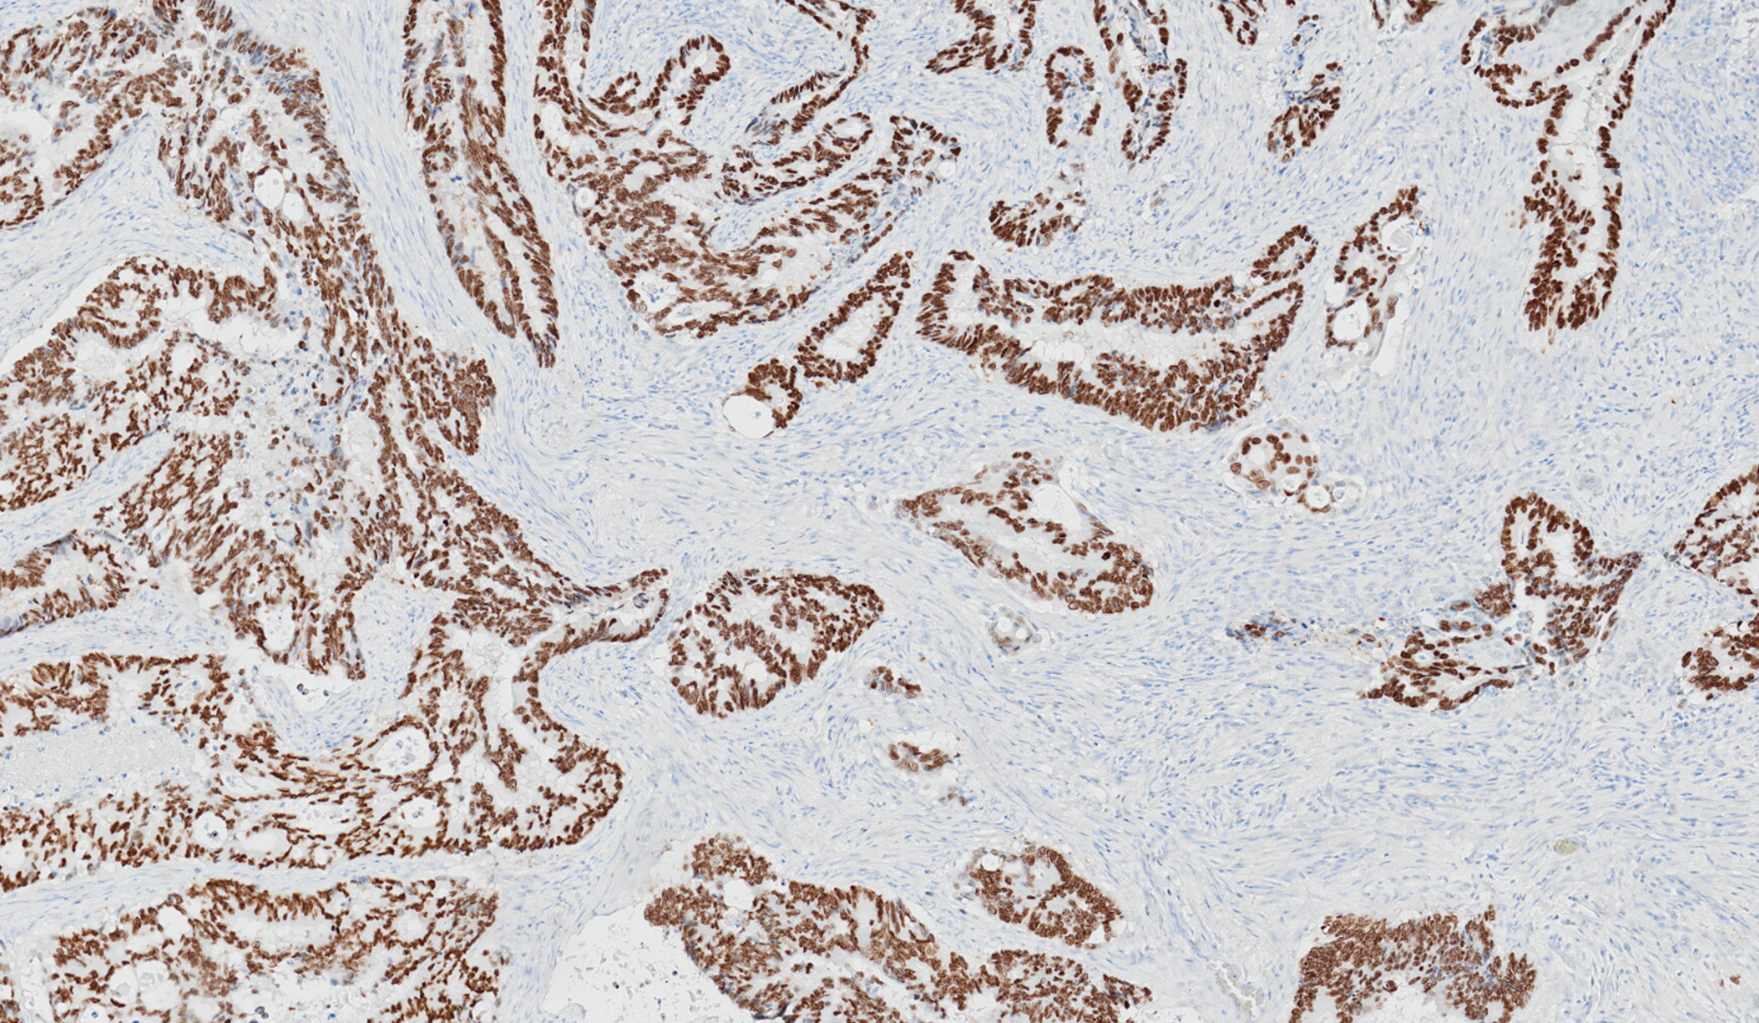

Utility of special AT-rich sequence-binding protein 2 (SATB2) in gastrointestinal tumour diagnostics

Learn how special AT-rich sequence-binding protein 2 (SATB2) supports accurate diagnosis of colorectal and other lower gastrointestinal tumours. Discover how SATB2 complements CDX2 to improve detection in Cancer of Unknown Primary (CUP) cases.